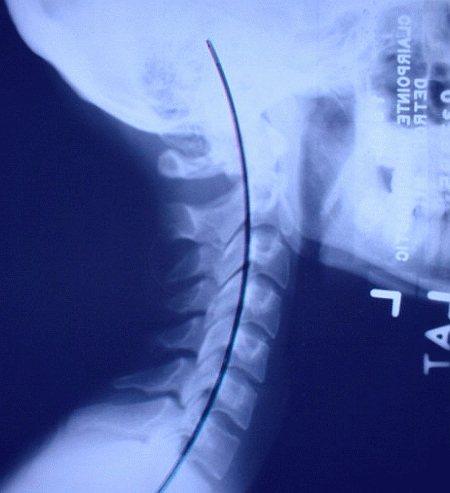

Best Pillow to Help Put the Curve Back in Your Neck When you are Sleeping

The best pillow is going to be one that allows you to have a curve in your neck while you sleep. This can be a pillow made from memory foam, fiber, or anything you like. The best one I recommend is the arc4life traction pillow. All of these types of pillows are going to involve some type of adjustment period since they are putting a contour in your spine when you sleep - Expect some neck soreness when you wake up the first few times possibly.